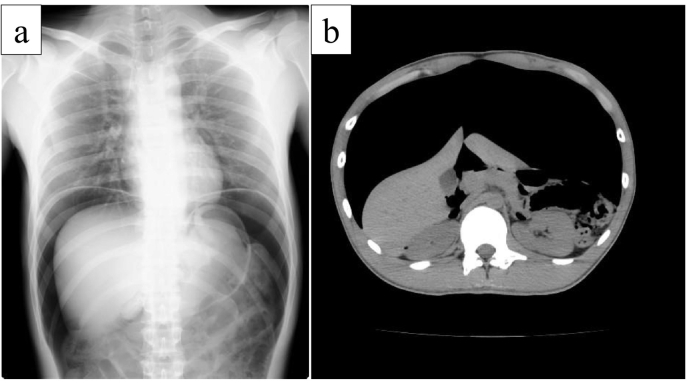

A 20-year-old male used a high-pressure compressed air machine to dust after working with his coworkers. The coworker started to play a prank, attached the compressed air to the patient's anus, and inserted the high-pressure compressed air transanally as a joke. Although he returned home once, he experienced gradual abdominal pain and consulted a former hospital. He underwent radiography and computed tomography (CT), which showed massive free air (Fig. 1a and b), and was diagnosed with perforation. The patient was admitted to our hospital. When he arrived at our hospital, he was in a clouded state of consciousness and pre-shock state. On general examination, he was in a state of respiratory distress and pallor, tachycardia (126/min) with tachypnea (49/min), and a blood pressure of 136/98 mmHg. The Glasgow Coma Scale score was E3 V3 M5. Abdominal examination findings were consistent with perforation peritonitis (distended abdomen, abdominal tenderness, and rigidity). Laboratory tests revealed a white blood cell count of 17,320 cells/mL, CK level of 741 IU/L, LDH level of 271 IU/L, and pH level of 7.253. He was diagnosed with perforation and acidosis, and emergency surgery was performed. On operative findings, the degree of contamination was mild with little dirty ascites and a massive air bubble inside the omental burs (Fig. 2a). Transverse colon perforation with extensive colon serosal tear (Fig. 2b and c) was observed. A schema of the operative findings is shown in Fig. 2d. He underwent double-barrel colostomy using a transverse colon perforation point for decompression and diverting the stoma at the ileum end (Fig. 3a) with serosal tear repair and abdominal cleaning drainage. Postoperative multidisciplinary treatment may have saved the patient's life. Finally, approximately 4 months after the initial surgery, the patient underwent colostomy and diverting stoma closure (Fig. 3b).

Fig. 1.

Preoperative image findings

a: Radiography revealed massive free air in the abdominal cavity. b: CT revealed massive free air and distention of the colon.

Severe abdominal distension, pain, and peritoneal signs, such as abdominal rigidity, tenderness, and rebound tenderness, are recognized as critical symptoms [5], [6] Peritonitis can be easily diagnosed because patients typically complain of abdominal pain and distension after exposure to compressed air. In addition, radiological examinations can reveal a distended colon or large amount of free air in the peritoneal cavity [7]. The patient in our case also visited a former hospital with complaints of abdominal tenderness and distention, and radiography and CT revealed massive free air in the peritoneal cavity. Although the patient exhibited pallor and tachypnea (respiratory rate 49/min), his other vital signs were stable. Therefore, emergency surgery was performed as soon as possible.